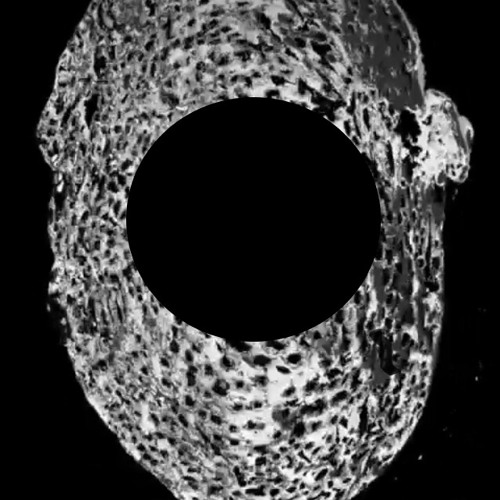

I made this in 2020 for Shallal Arts out of a variety of British Bat calls. It includes; Greater Horseshoe, Pippistrell, Noctule, Serotine, Myotis and Brown Long-eared